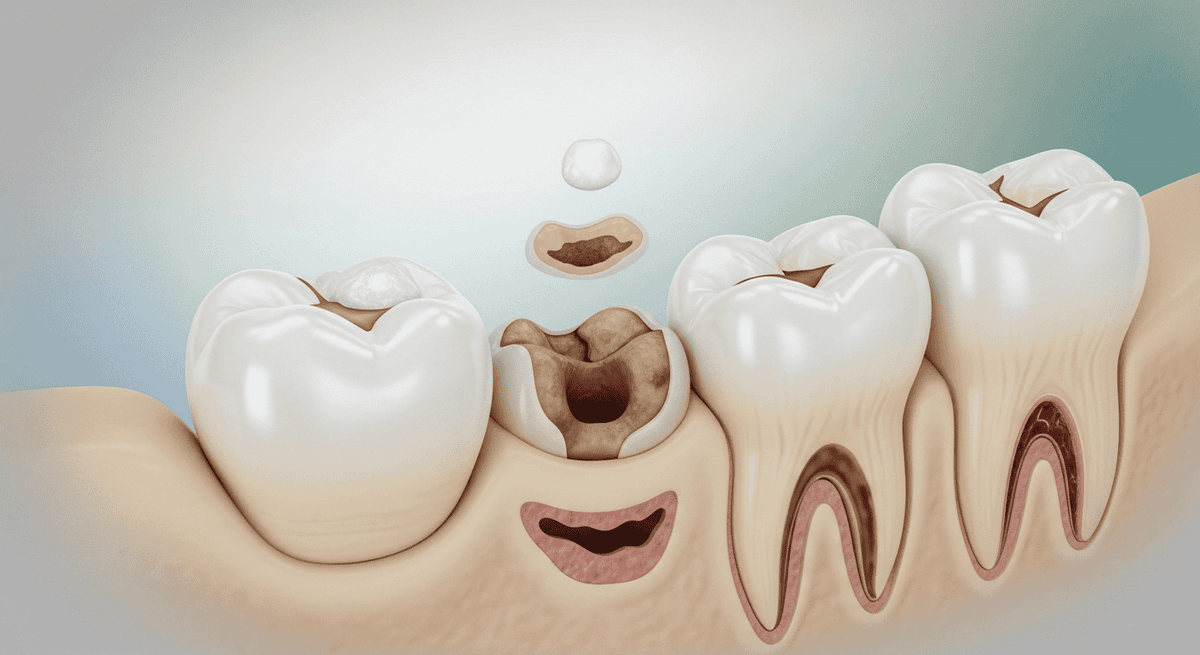

在牙科諮詢中,很多病人第一反應是詢問「哪間診所最平?」。但在醫療決策上,單純的低價往往隱藏著巨大的長遠成本。補牙的核心價值不在於「填滿那個洞」,而在於防止「微滲漏 (Micro-leakage)」,這是保護牙髓(牙神經)免受細菌侵蝕的關鍵屏障。什麼是微滲漏?補牙的頭號殺手

樹脂補牙是一個精密的化學黏合過程。如果醫生在過程中隔濕(Isolation)不夠嚴謹,例如受患者口水、霧氣甚至是呼出的水氣污染,補牙物料與真牙之間就會產生肉眼看不見的細微縫隙。這會導致:- 二次蛀牙 (Secondary Caries):細菌沿縫隙進入,在看似完好的補粉底下悄悄蛀蝕。

- 牙髓發炎:細菌深入牙本質小管,引發不可逆的神經發炎。

- 結構崩解:黏合力失效,導致補粉脫落或牙齒垂直劈裂。

牙科治療最講求「病向淺中醫」。若因預算問題推遲補牙,未來的經濟負擔將呈指數級增長:- 第一階段(初期淺層蛀牙): 一般補牙 (約 HK$800 - $1,200),保留 95% 真牙,過程幾乎無痛。

- 第二階段(細菌侵入牙髓): 需進行 杜牙根治療 (Root Canal) + 牙套,費用飆升至 HK$12,000 - $20,000。

- 第三階段(牙齒崩裂): 只能剝牙並進行 植牙 (Implant),總開支約 HK$25,000 - $35,000,是初期補牙費用的 30 倍。